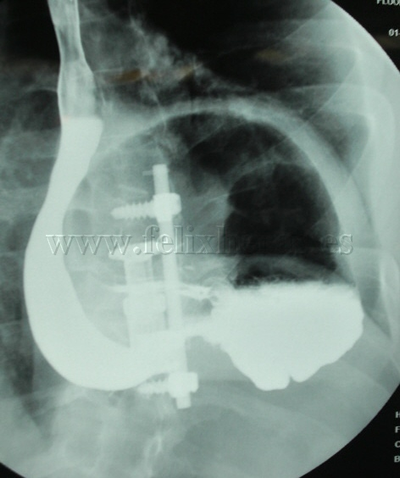

Hernia diafragmática traumática